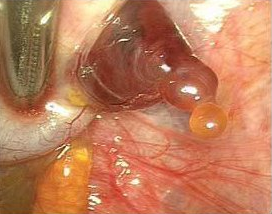

Непосредственно перед началом процесса выхода яйцеклетки на доминантном фолликуле образуется бугорок. Он хорошо просматривается на УЗИ аппарате.

Первым признаком начала овуляции считается величина доминантного фолликула (значение находится в пределах от 18 до 21 миллиметров). Помимо этого, возможно перепроверить и другой факт, например, образовавшееся желтое тело означает, что овуляционный процесс прошел вполне нормально.

Данный способ является самым достоверным, потому что просчитать день начала овуляционного процесса благодаря фолликулограмме – очень удобно. Так, врач будет наблюдать за динамикой и разростаемостью,созреванием фолликул и выходом яйцеклетки.

- Росте и созревании фолликула, который будет доминантным перед началом овуляционного периода;

- Появлении свободных жидкостей по окончании овуляции;

- Разрушении на стенках основного фолликула.

- Образовании желтоватого тела именно в той зоне, где созревает доминантный фолликул.